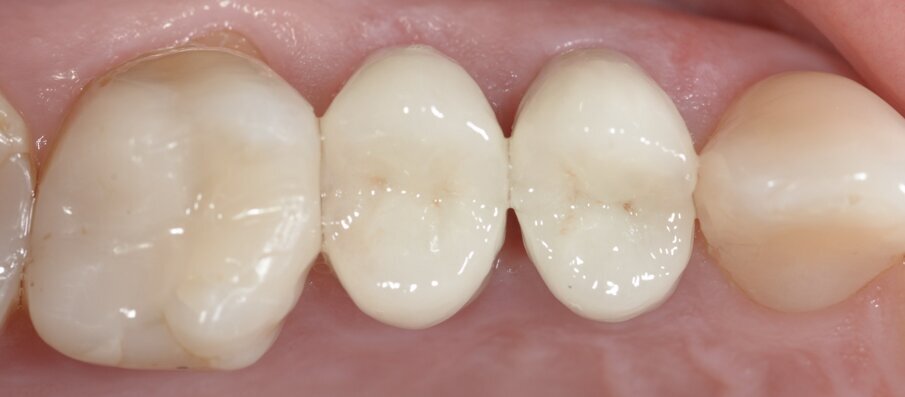

Dopo la prova, il restauro finale è stato cementato in bocca utilizzando vetroionomero, Fuji One (GC). Le immagini finali mostrano un follow up postoperatorio della situazione clinica a due e dieci mesi e una gengiva perfetta (Figg. 6 e 7).

Fig. 6: Situazione postoperatoria dopo due mesi.

Fig: 7: Controllo dopo dieci mesi.